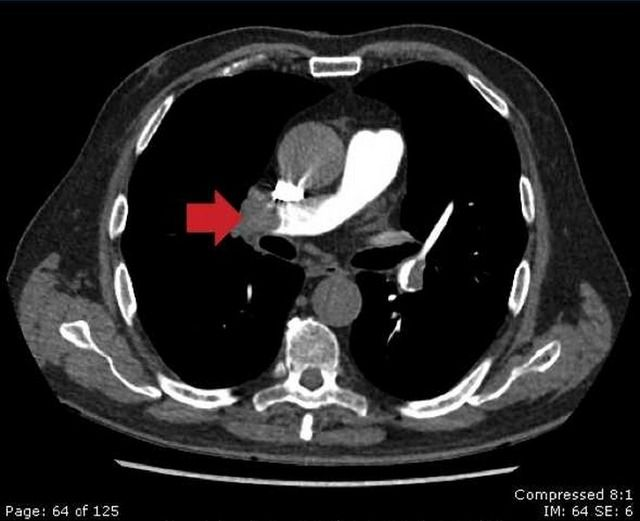

四大胸痛杀手